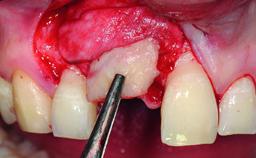

| Bone Augmentation | Simultaneous|Vertical |

| Augmentation Materials | Autogenous chips|Xenogenous|Membrane |

| Bone Volume | Deficient vertically or deficient vertically AND horizontally |